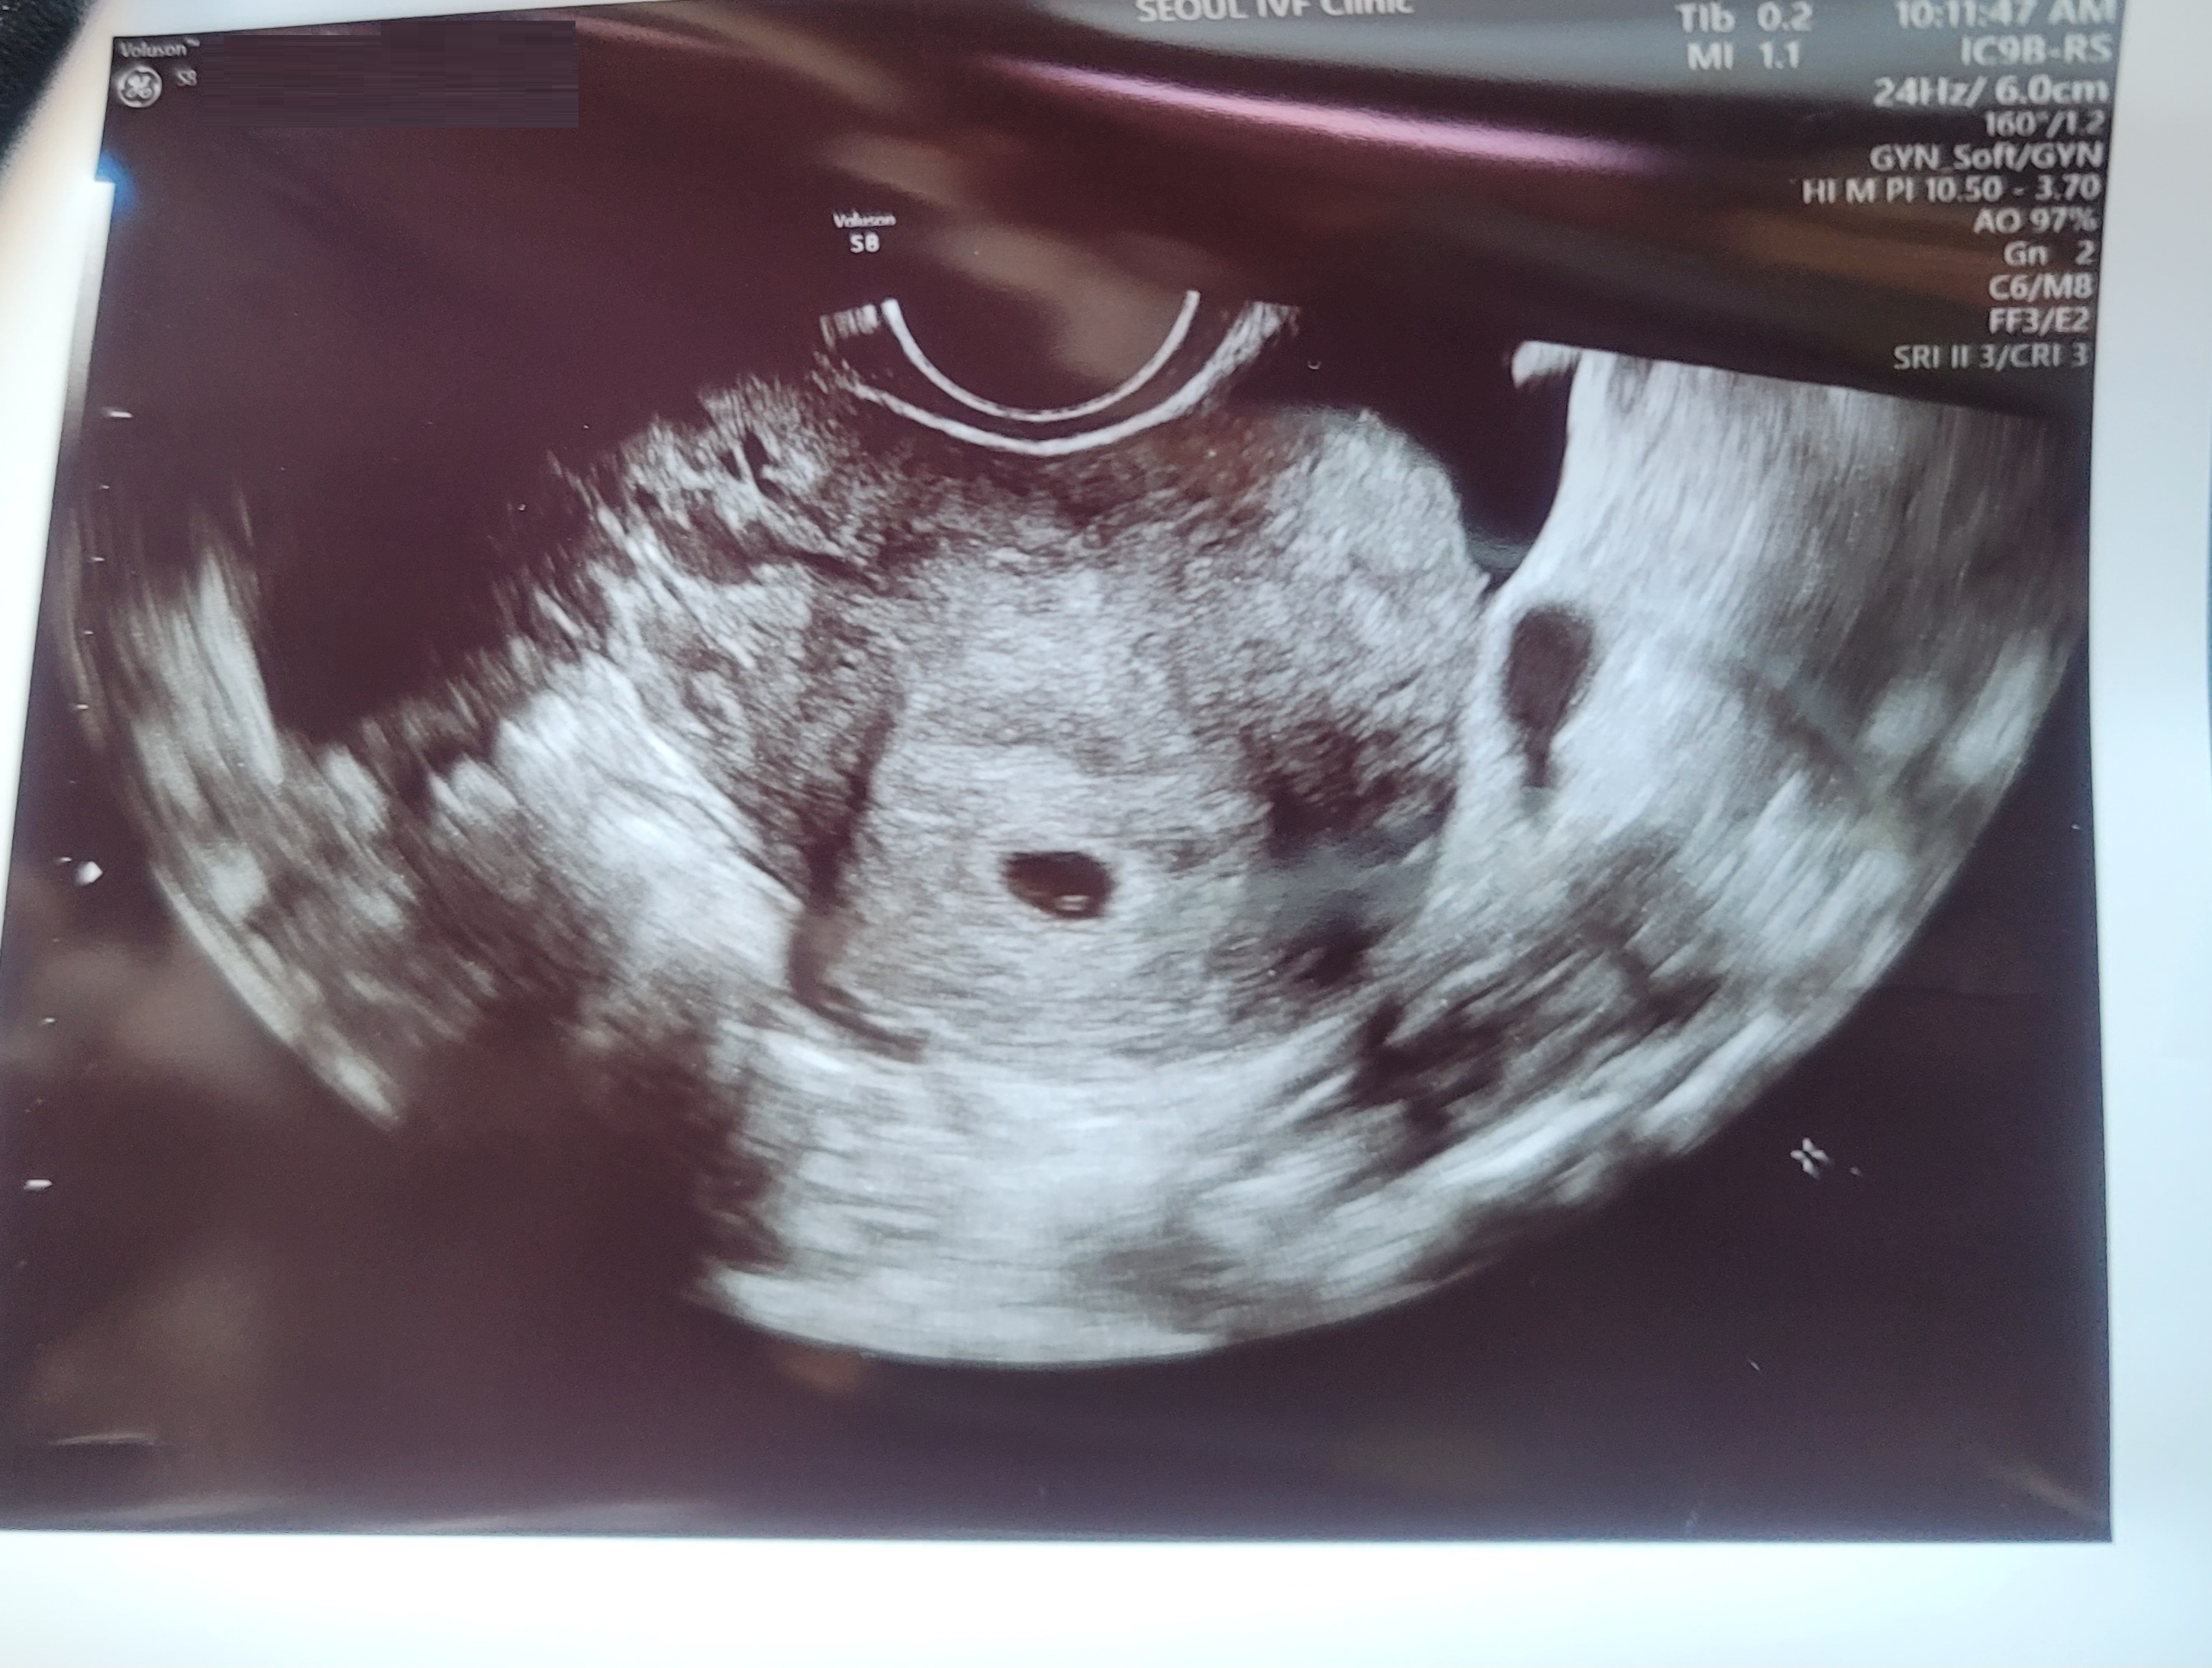

| 가슴 떨리는 임신 이야기를 공유해 주세요. | 3번의 난자채취와 3번의 PGT 검사를 진행했지만 결과가 좋지 않아 마음이 지쳐갈 때, 신선 3차에서 처음 시도한 3일배아 신선이식에서 임신에 성공했어요. 흐릿한 임테기 두 줄을 처음 보았던 그 순간이 아직도 잊히지 않습니다. 지금은 꿈처럼 10주차에 접어들었어요. |